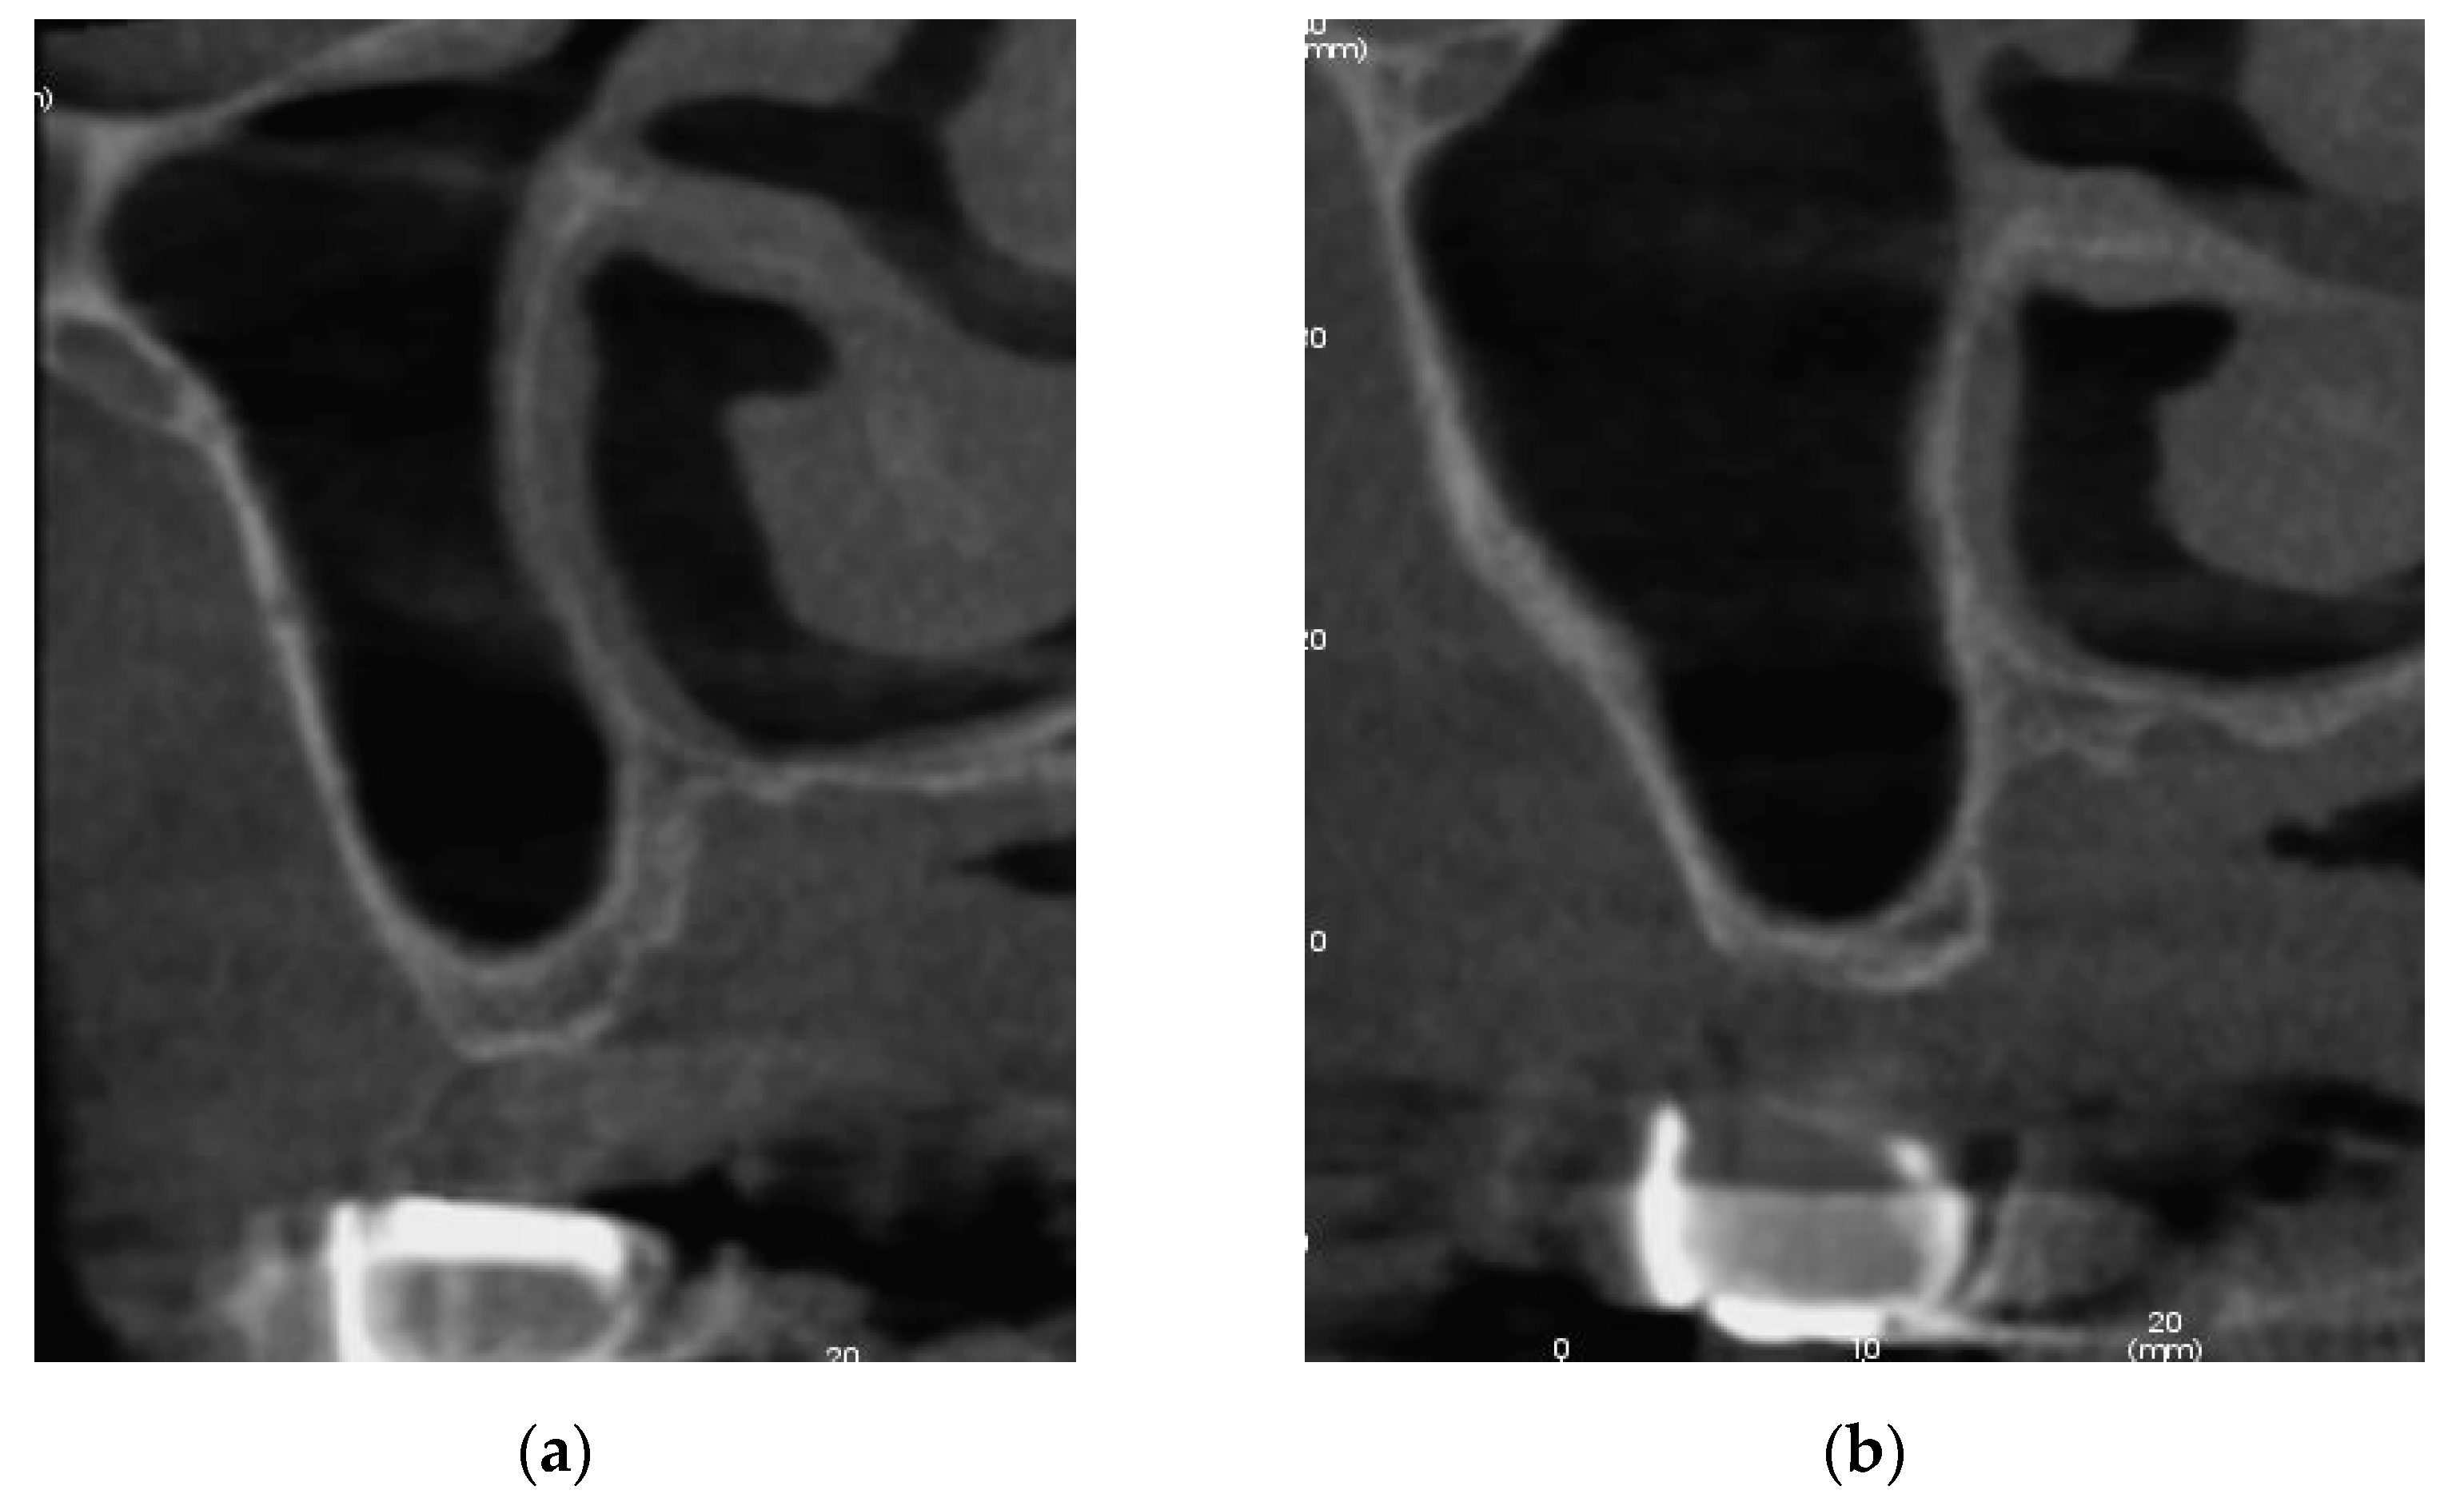

3.1. Patient #1

3.1.1. Surgery

3.1.2. Follow Up